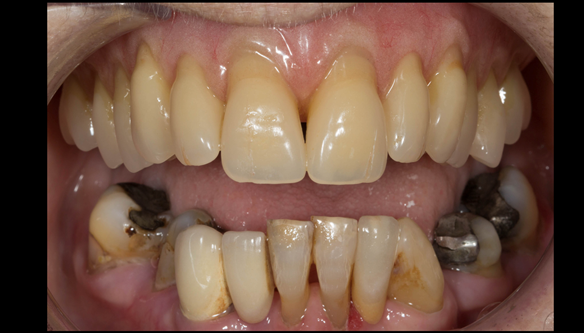

- The remaining natural upper natural teeth and lower back molars were heavily restored having generalised periodontitis stage 4 Grade C. Some of the teeth exhibited caries. The prognosis for these teeth ranged from dubious to hopeless.

- The upper and lower acrylic based partial dentures exhibited suboptimal extension of the flanges and saddles. They had poor retention, support, stability and tissue fit.

- The patient had a high smile line showing 5mm or more alveolar soft tissue above the upper front teeth during social interaction.

The clinical situation and treatment process is shown in detail below with photographs. In addition, threre is a link to the a 45 minute webinar I gave explaing this case. I provided the clinical work and Rowan Garstang provided the technical work.